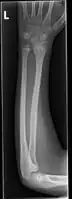

Side view of bowing fractured radius and ulna